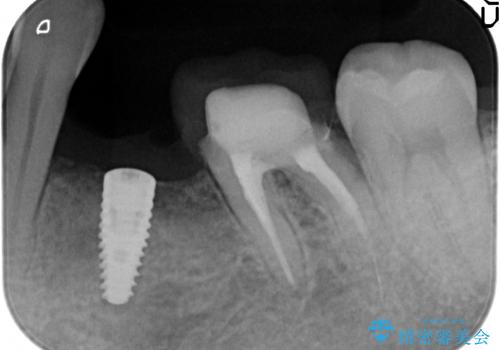

インプラント 左下奥歯の咬み合わせの改善

- 左下の歯並びが悪く、左側で物が咬みにくいので診て欲しいといらっしゃった方の症例です。

歯列矯正は御希望されなかったため左下4、5番目の歯を抜歯し、インプラントによる欠損補綴を行いました。

左下6も再根管治療後、オールセラミッククラウンによる補綴を行いました。